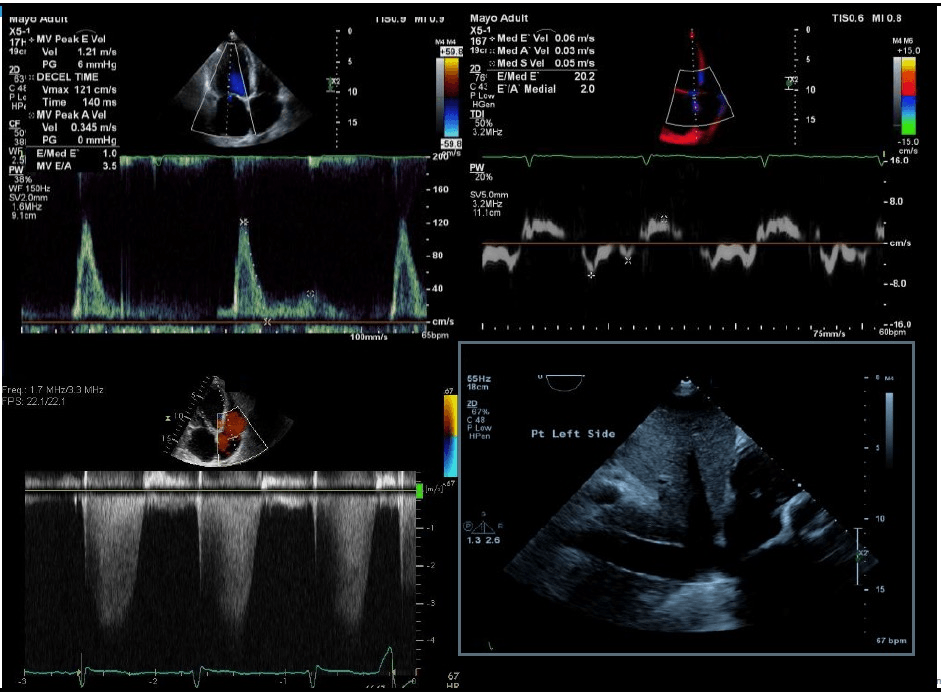

The diastolic function in this patient with LVH

What is Grade 3 diastolic dysfunction?